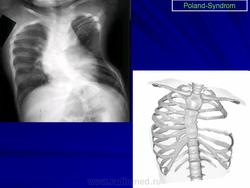

Синдром Поланда (СП) представляет собой комплекс пороков, включающий отсутствие большой и малой грудной мышц, синдактилию, брахидактилию, ателию (отсутствие соска молочной железы) и/или амастию (отсутствие самой молочной железы), деформацию или отсутствие нескольких ребер, отсутствие волос в подмышечной впадине и снижение толщины подкожно-жирового слоя. Отдельные компоненты этого синдрома впервые были описаны Lallemand LM (1826) и Frorier R (1839). Однако назван он по имени английского студента-медика Alfred Poland, который в 1841 году опубликовал частичное описание данной деформации. Полную характеристику синдрома в литературе впервые опубликовал Thompson J в 1895 году.